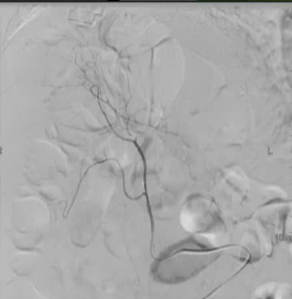

病例1 70/40 mmHg

病例1 20μg Arterenol (去甲肾上腺素) 155/85mmHg

|

激发下 |

栓塞后 |